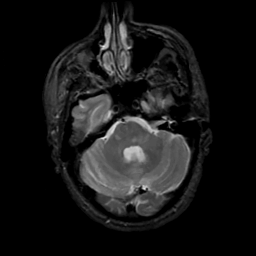

MR Study #5, March 10, 1991 -- Slice #14

[Home][Help][Clinical][Tour 1][Tour 2] Slice 14